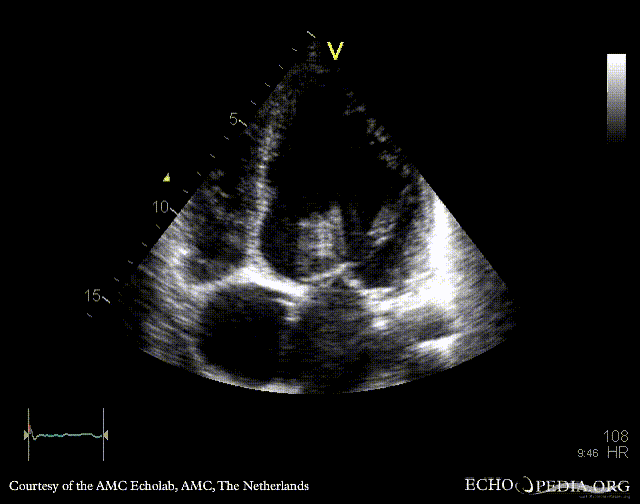

E00802.gif E00803.gif

PLAX: dilated left ventricle, poor function, vegetation on aortic valve PLAX with zoom: vegetation on aortic valve